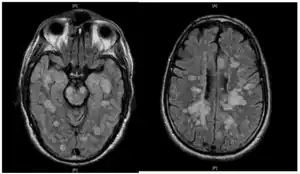

| Fulminating ADEM showing many lesions. The patient survived, but remained in a persistent vegetative state | |